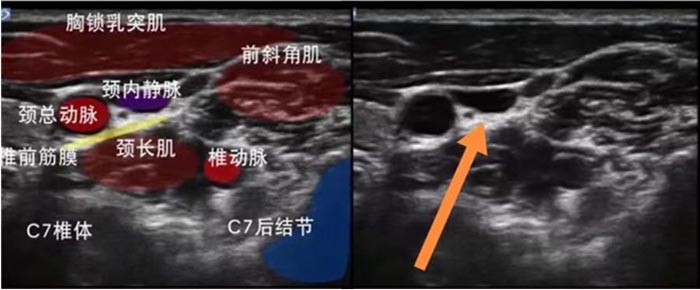

2.超声引导下星状神经节阻滞:

星状神经节阻滞是通过降低人体交感神经兴奋性,帮助患者减少停用安眠药物后的失眠反弹发生率,减轻戒断安眠药的躯体症状以及CBTI治疗2-3周出现的白天困倦感。操作在超声引导可视下进行,安全效果可靠。